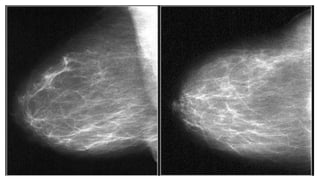

• #17 an example of a focal asymmetry seen on MLO and CC-view. Local compression views and ultrasound did not show any mass.

• #18 This is an example of global asymmetry in the breast. The entire right breast is denser than the opposite breast. This finding has been present and stable for 4 years. No evidence of solid nodules in the ultrasound study (not shown), only simple mammary cysts were visualised bilaterally, compatible with BI-RADS II (benign findings).